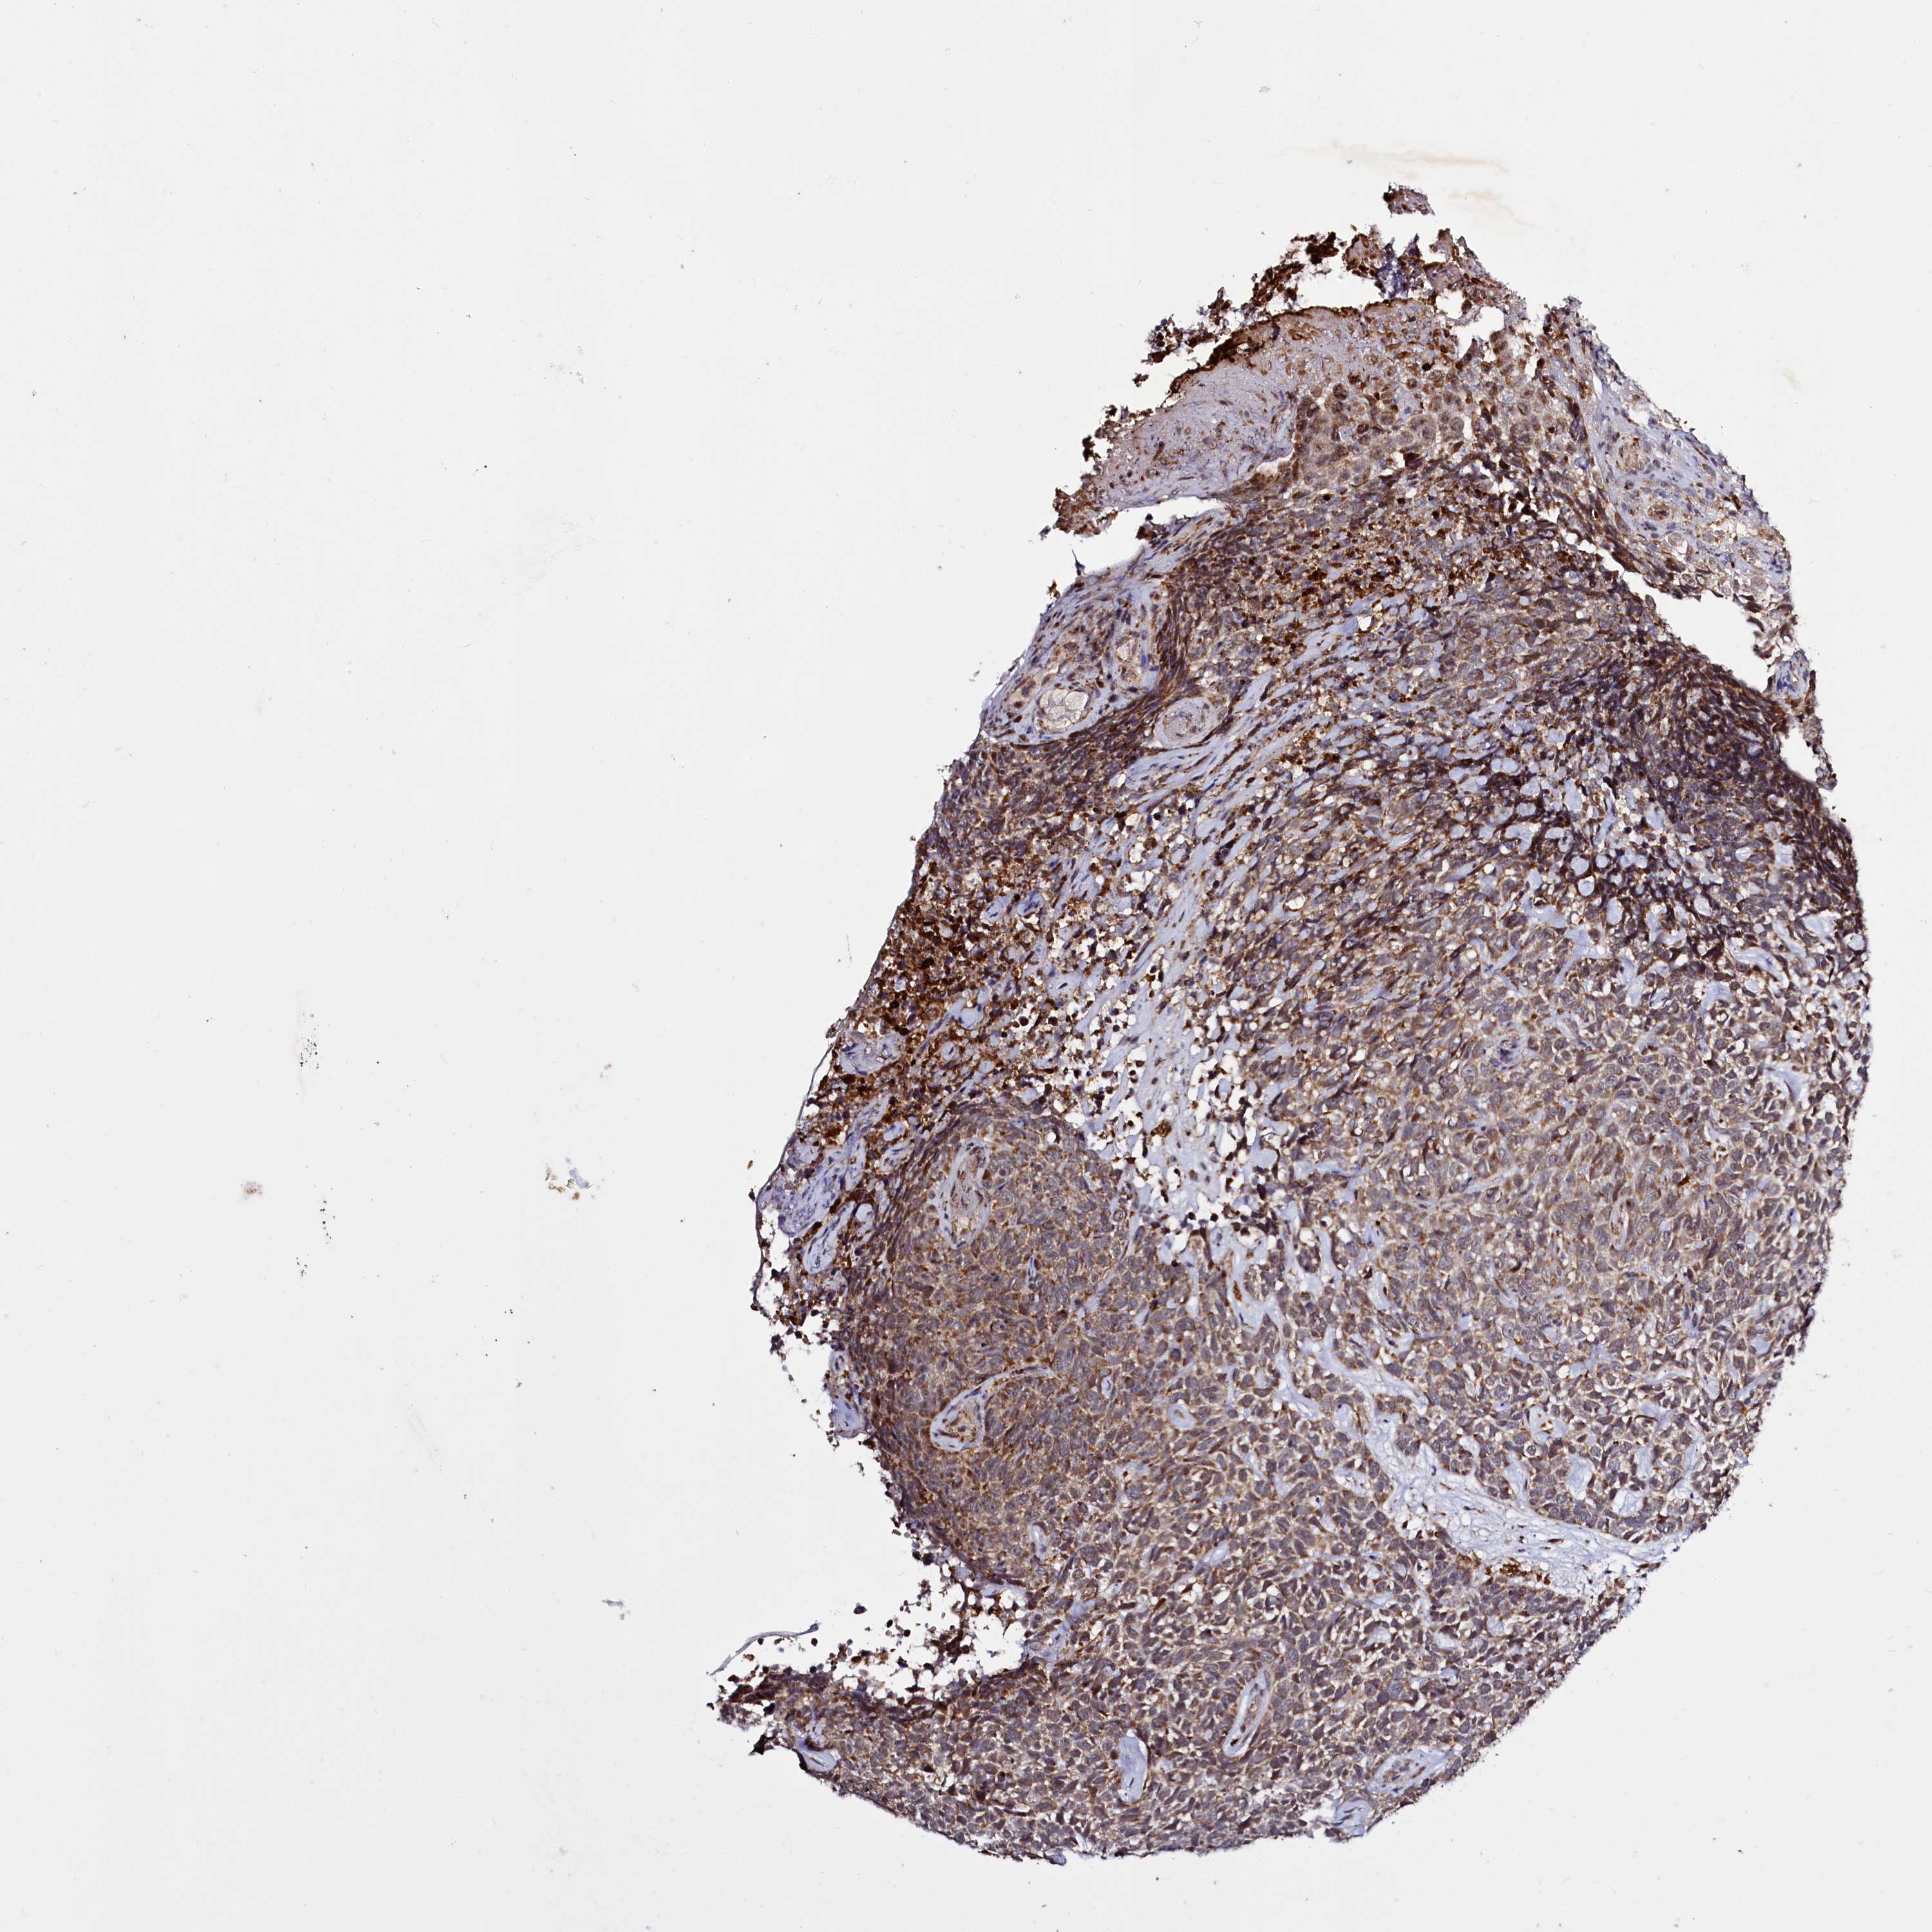

SKIN CANCER - Protein expressioni

A mouse-over function shows sample information and annotation data. Click on an image to view it in a full screen mode. Samples can be filtered based on level of antibody staining by selecting one or several of the following categories: high, medium, low and not detected. The assay and annotation is described here.

Each image is clickable and will lead to virtual microscopy that enables deeper exploration of all samples and also displays staining intensity scores, fraction scores and subcellular localization as well as patient and tissue information for each sample.

Antibody HPA039015

Antibody HPA039016

Squamous cell carcinoma, NOS

Squamous cell carcinoma, metastatic, NOS